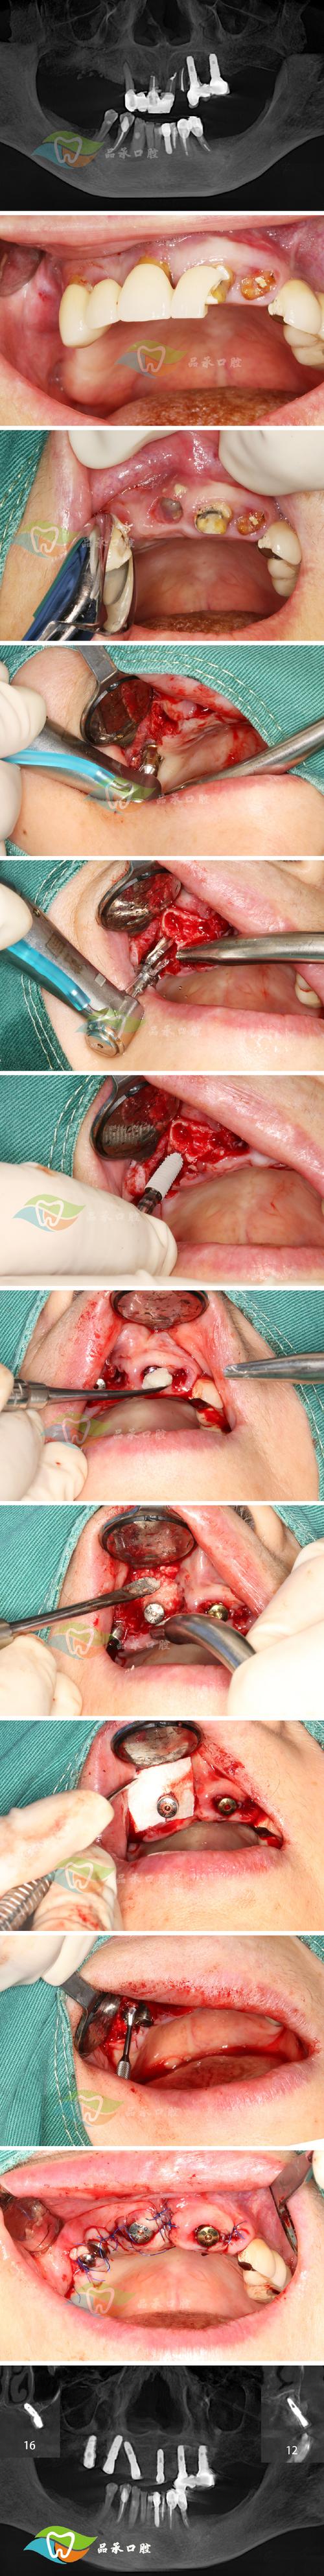

此阶段植骨材料应完成骨改建,与自体骨形成稳定骨结合,若失败则表现为明显的骨吸收与种植体并发症。种植体相关失败,若已植入种植体,可能出现种植体松动、叩痛阳性,周围牙龈红肿、溢脓,形成深牙周袋(深度>5mm),甚至种植体脱落,提示种植体周围炎或骨整合失败。植骨区骨量不足,CBCT检查可见植骨材料被大量低密度影替代,植骨区域体积明显缩小,与周围自体骨界限清晰,无骨小梁形成,骨密度低于正常骨组织。功能障碍,因骨量不足导致修复体无法戴入或固位不良,咀嚼效率下降,甚至出现颞下颌关节紊乱(如关节弹响、疼痛)。

通过专业检查可更准确判断植骨是否成功,具体如下表:

| 检查类型 | 异常表现 |

|---|---|

| 临床检查 | 探诊出血(+)、溢脓,种植体动度Ⅰ度以上,植骨区黏膜压痛(+),邻牙叩痛(+) |

| 影像学检查(CBCT) | 植骨材料与自体骨间可见低密度分隔线,植骨区骨密度低于周围骨,植骨材料体积缩小>30%,骨皮质连续性中断 |

植骨不成功的表现具有阶段性特征,早期以疼痛、感染症状为主,中期表现为黏膜异常与咬合不适,晚期则以骨吸收、种植体失败为核心,需结合临床症状、临床检查及影像学结果综合判断,一旦出现异常,应及时复诊,明确失败原因(如感染、材料选择不当、患者自身因素等),并采取针对性处理(如抗感染、植骨材料取出、重新植骨等),以避免进一步损伤。